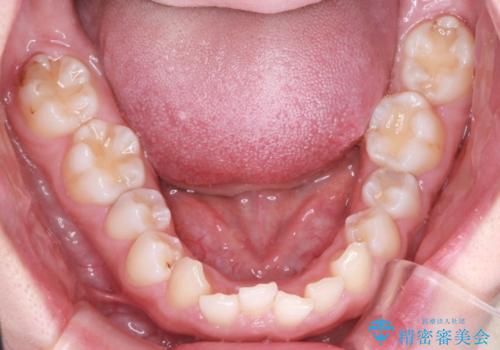

- 患者様は、ディープバイト(深い噛み合わせ)と、咬合平面の左下がりが気になるとのことでご来院されました。診断の結果、非抜歯で治療可能と判断し、透明なマウスピース型矯正装置「インビザライン」を用いる方針としました。治療では、歯列全体の調整を行いながら、咬合平面の水平化を重点的に進める計画を立案しました。2年間で計画的にマウスピースを交換し、左右のバランスと噛み合わせの改善を目指しました。

ディープバイトの矯正は、噛み合わせが深くなりがちなため、細心の注意を払いながら進める必要があります。本症例では、奥歯の高さを調整しつつ前歯の噛み合わせを浅くすることで、全体の咬合バランスを整えました。また、咬合平面の左下がりを修正する過程で、歯列に不均等な力がかからないよう、インビザラインのアタッチメント配置を最適化しました。患者様には装着時間を守っていただき、治療が計画通り進むよう協力をお願いしました。治療終了後には、リテーナーを装着して安定性を確保しました。